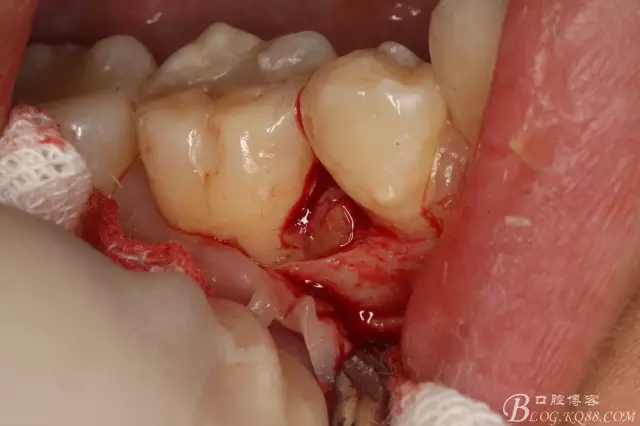

圖7.翻小瓣。暴露45牙根斷面

圖8.高速球鉆去骨約3mm.

圖9.暴露45頰側(cè)根面約1/2.牙根與44、46牙根緊緊相鄰。無法直接用挺。